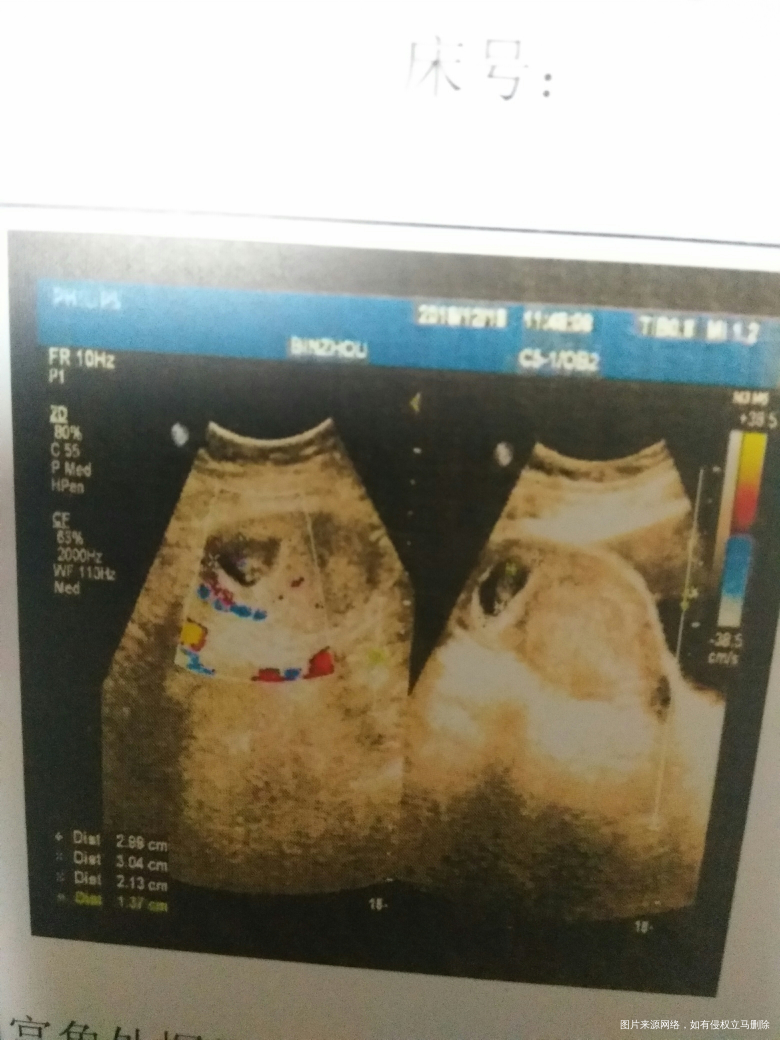

4楼你好,宫角妊娠属于异位妊娠,不建议继续怀孕

5楼你好过一段时间再做个彩超有可能位置会变化到宫腔,如果还是在宫角的话,建议你不再继续妊娠。宫角妊娠是一个疑为妊娠。有危险。